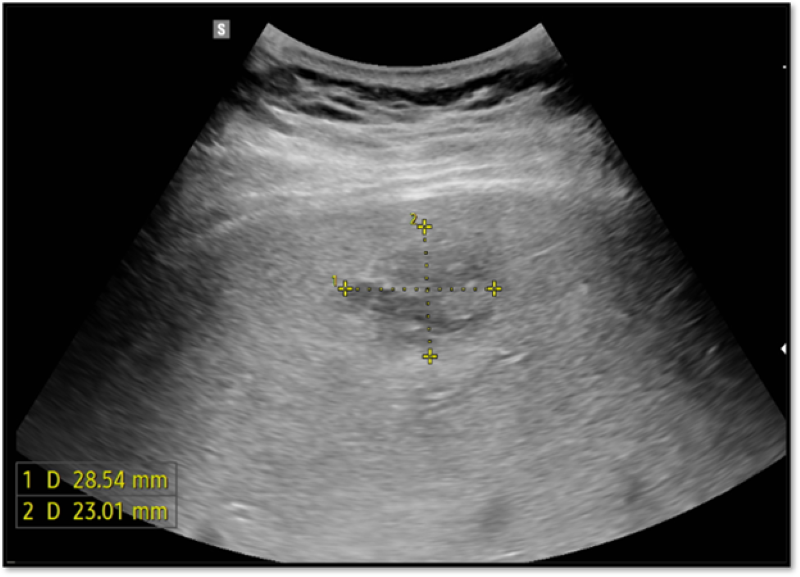

Kết quả xét nghiệm có CRP và nhiều chỉ số khác cao vượt ngưỡng bình thường cho thấy tình trạng nhiễm trùng. Trên siêu âm và cắt lớp vi tính ổ bụng cho thấy hình ảnh ổ dịch hỗn hợp âm gan phải, theo dõi áp xe gan.

Trên siêu âm phát hiện hình ảnh ổ dịch hỗn hợp âm gan phải, theo dõi áp xe gan

- Siêu âm có vai trò phát hiện bất thường ở ổ bụng và hỗ trợ điều trị (theo dõi hiệu quả điều trị, chọc hút ổ mủ);